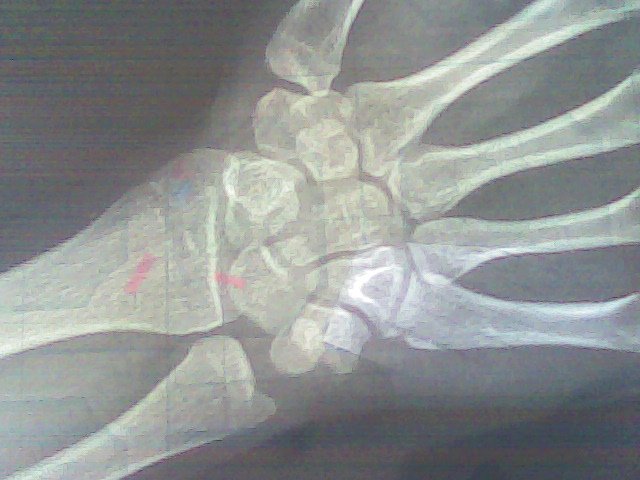

帮忙看一下骨龄片 我15岁,女生,现身高153.5cm.母亲身高151cm,父亲身高165cm.月经初潮13岁半

医生说你的骨头完全闭合了么????这个我也不太会看